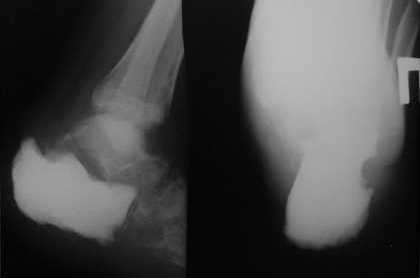

Б-й Т. 25 лет. Обратился впервые 04.11.09 с новообразованием пяточной

кости. Выполнена биопсия, установлен диагноз:

высокодифференцированная хондросаркома.

произведена экзартикуляция пяточной кости, замещение дефекта

цементным спейсером.